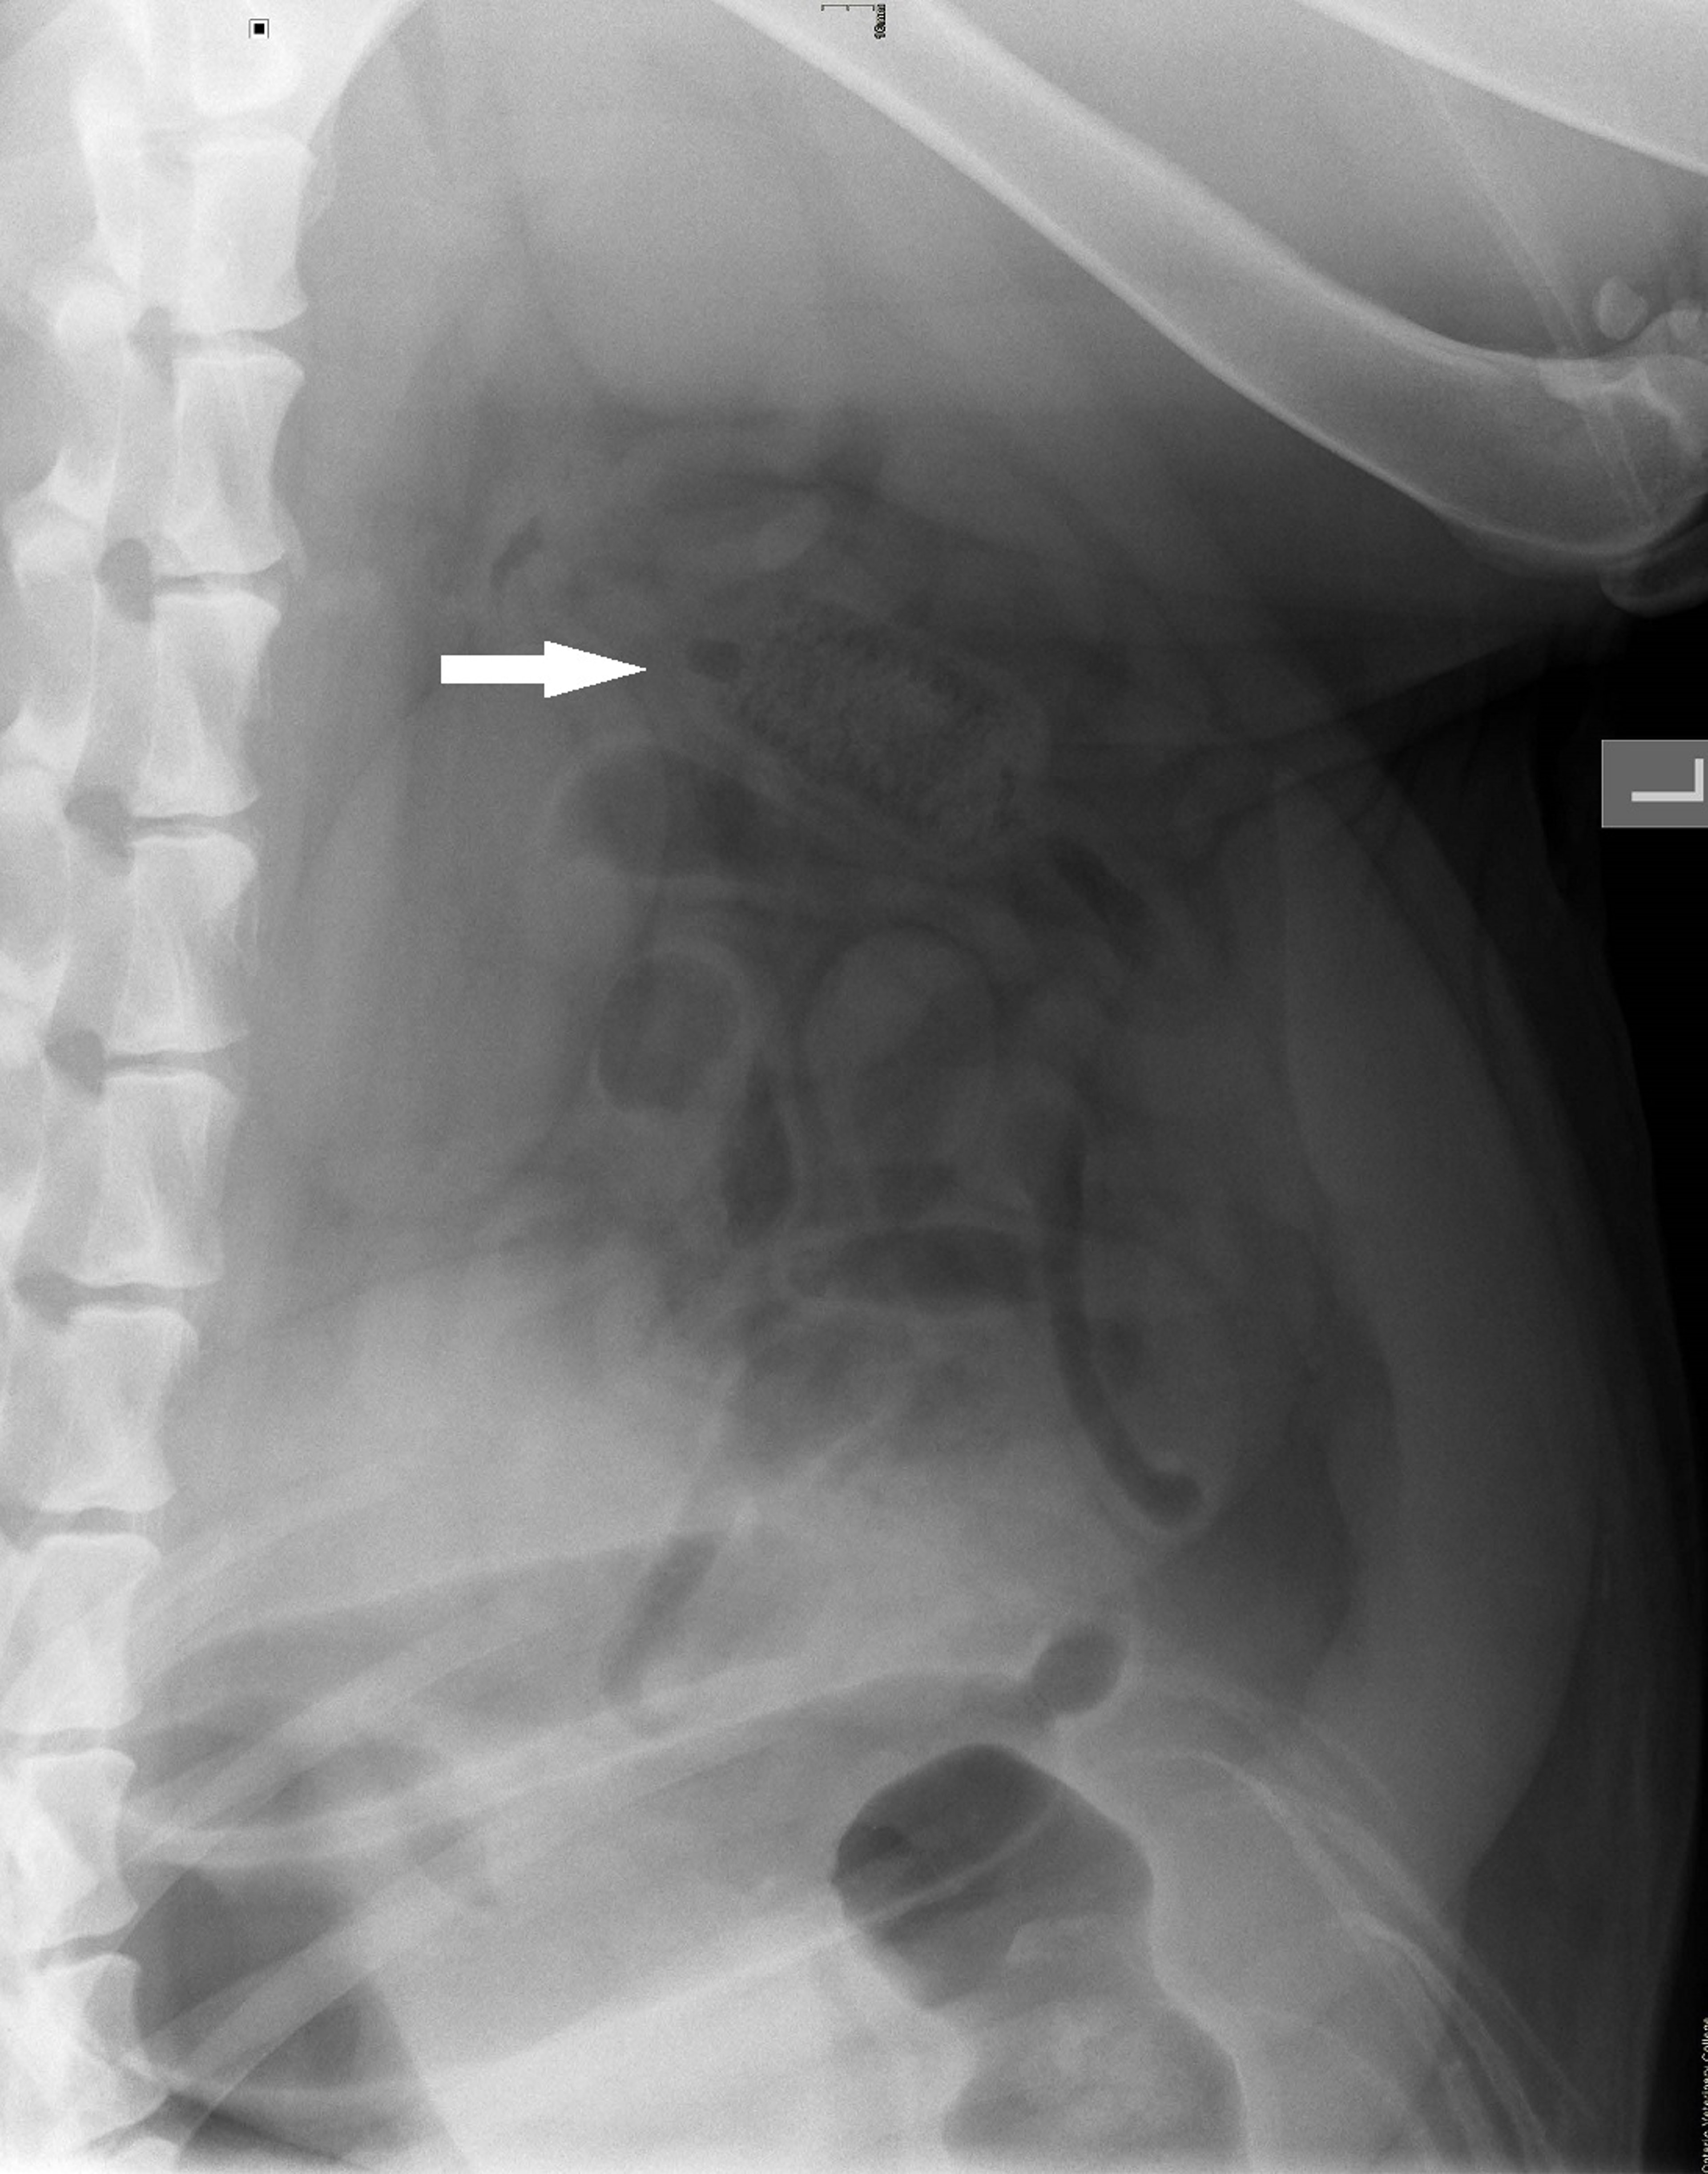

Lateral abdominal radiograph of a two-year-old Labrador Retriever with a corncob small intestinal obstruction.